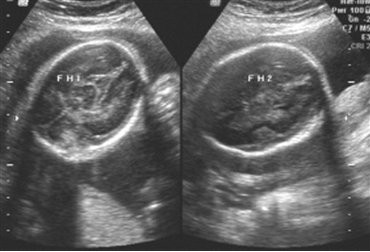

怀孕九个月胎儿入盆图谁知道是什么样的呢?就是这个时候胎儿已经入盆了 胎儿入盆会感觉到胎儿下降,呼吸

怀孕7个月胎儿b超图介绍